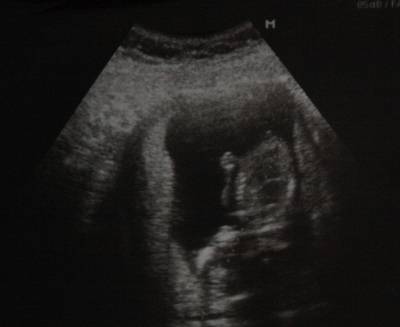

15 tydzień